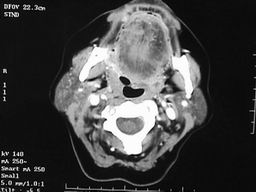

Dutina ústní

Chirurgie – dutina ústní

Perorální resekce

- Omezené indikace – dobře přístupné tumory

Zevní přístupy šetřící mandibulu

- Kombinovaný přístup – „pull-through“

Zevní přístupy s mandibulotomií (-ektomií)

- Transmandibulární bukofaryngektomie - mandibulární split

- Marginální resekce mandibuly

- Segmentální resekce mandibuly